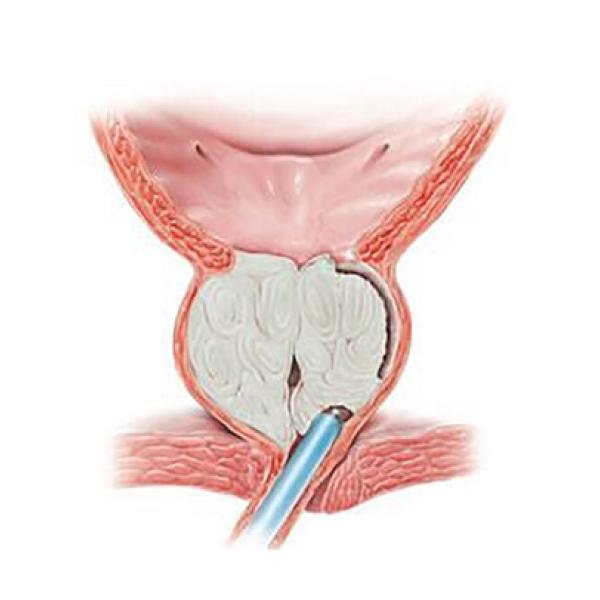

- Предстательная железа

- Предстательная железа

- Аденома простаты

- Доброкачественная гиперплазия предстательной железы

- ТУР простаты (трансуретральная резекция предстательной железы)

- Трансуретральная резекция предстательной железы (ТУР простаты) – восстановление и выписка